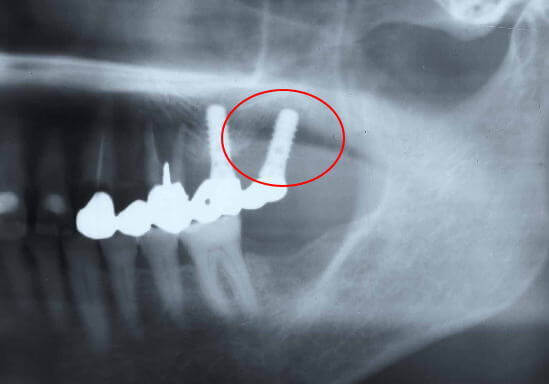

インプラント周囲の骨が溶かされているレントゲン写真

インプラント周囲に炎症が起こり、インプラント周囲の骨が溶かされている